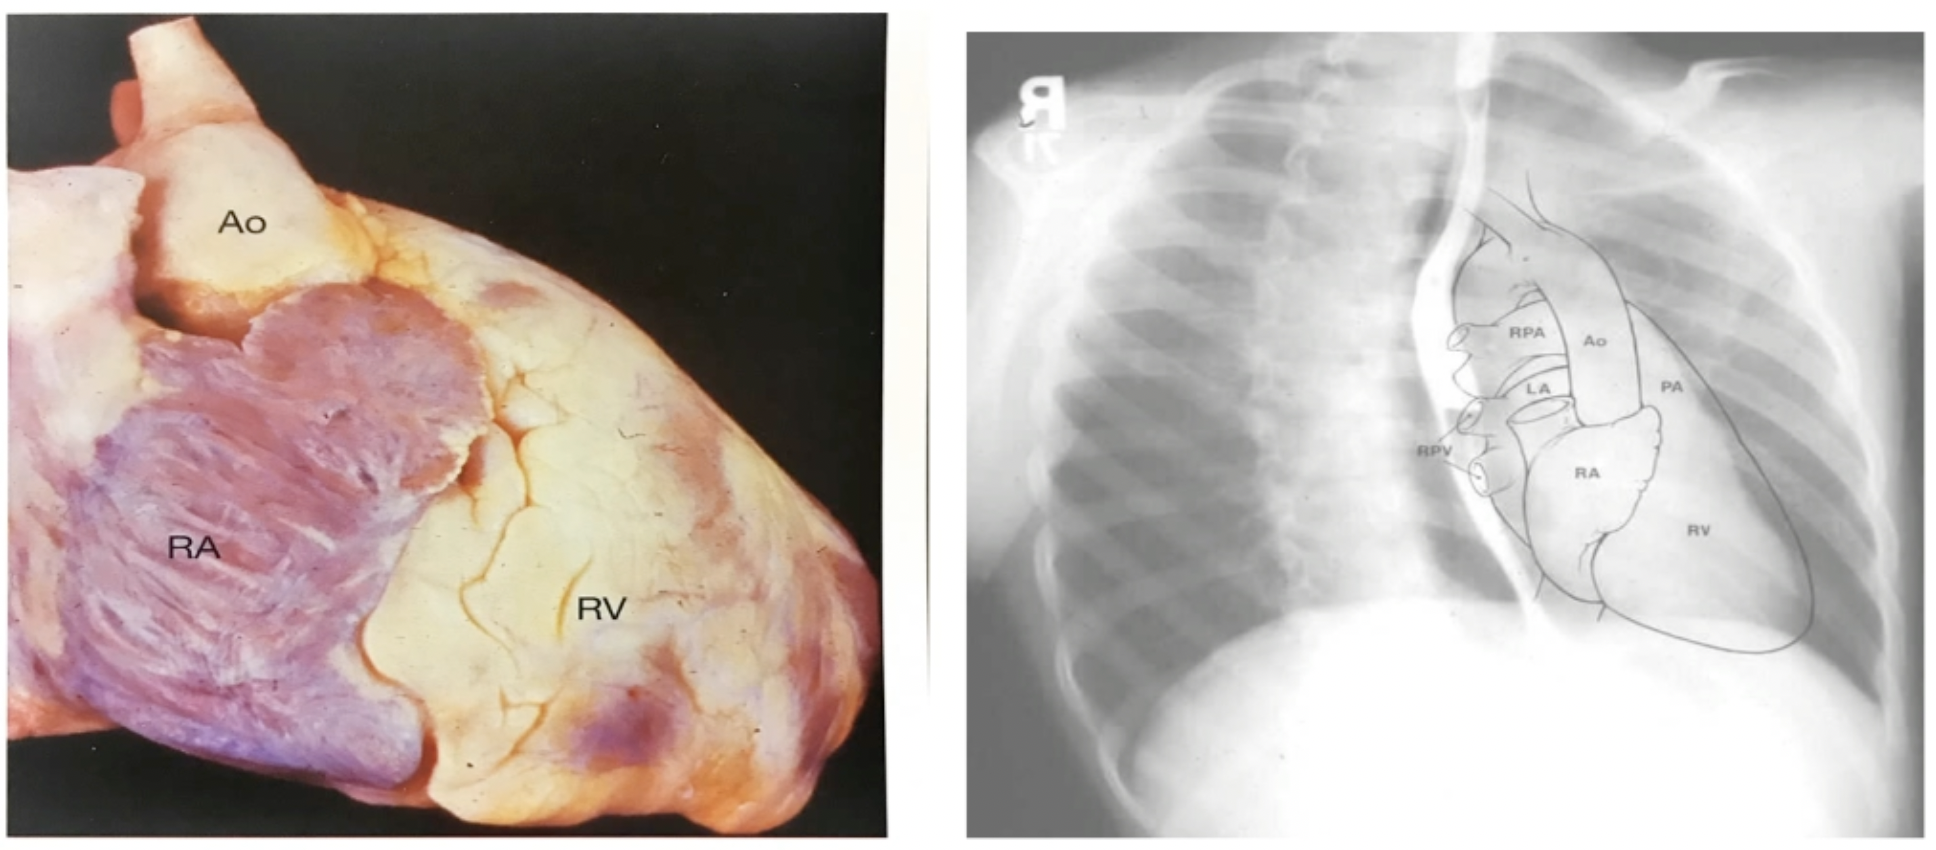

# 右前斜 RAO

- 观察右心房、肺动脉主干、右心室

- 胸骨在心脏前面

- 脊柱和食管在心脏后面